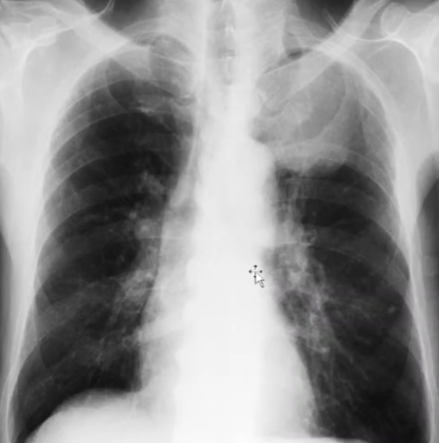

Rx toracică, incidență P-A

DESCRIERE:

la niv. întregului hemitorace drept → opacitate extinsă, nesistematizată, de intensitate mare, omogenă

caracter expansiv → împinge traheea și mediastinul de partea opusă

diafragm deplasat în jos

lărgirea spațiilor intercostale

umplerea spațiului costo-diafragmatic

DX: pleurezie masivă

DD: atelectazie → caracter retractil